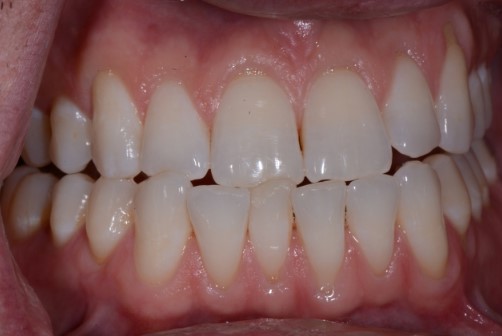

Cases of attrition are often present in the unbalanced environment where a patient is naturally balancing themselves. The question here: What is the long-term consequence? Clinically, this can show anywhere from one canine with a flat incisal edge to an entire arch of teeth with completely flattened cusp tips. The worn area of one tooth or arch will have an equal and opposite pattern of wear in the other tooth or arch.

The idea is to look beyond a single tooth and appreciate the system of joints, muscles, and teeth. What impact, if any, does the imbalance have on the patient for the short term and the long term? How long will your dentistry last in the current environment?

The great thing about gaining a respect for balance is every dentist can implement what is learned on every patient. Begin to gather information as to what kind of system that single tooth is in. How balanced is the environment? How destructive is the environment?

As dentists, we all treat imbalance differently depending on our knowledge, skill, and comfort level. Treatment could include observation, tooth adjustment, diagnostic casts, splint therapy, equilibration, etc. However, every dentist can provide better treatment by simply having a respect for how a balanced system can benefit a patient. Dentistry is much more predictable and fun when we can place good dentistry in a good and balanced environment.